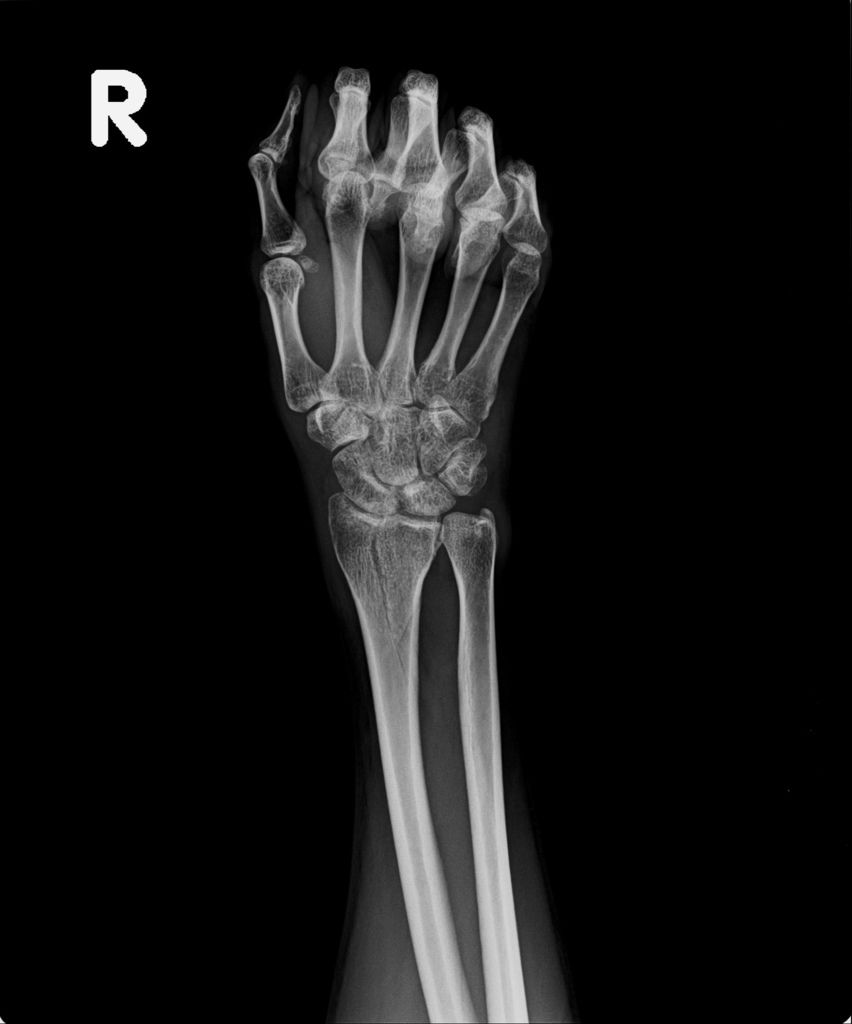

之後,我去照了X光,因為一個月前照X光,感覺已經快好了,我以為今天去照,骨頭應已癒合的差不多了。結果照出來之後,竟然還能看的到裂痕,讓我大吃一驚。唉....可能要等一陣子才會好。

今日所拍攝的X光照↓

最近四次所拍的X光↓